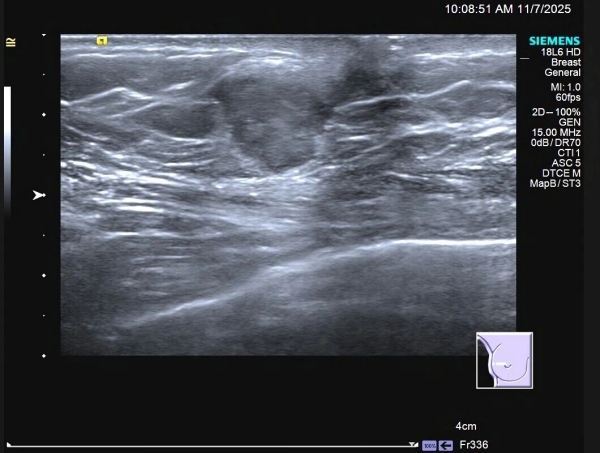

患者 C 先生,59 岁,因触及右乳肿物来到门诊部就诊,专科 B 超显示:右乳外侧近乳头处可见一低回声肿物,形态不规则,边缘模糊、成角,提示乳腺癌可能性大(BI-RADS:4C)。

在医生建议下,C 先生行 B 超引导下粗针穿刺活检术,病理显示:「浸润性癌」!

✦乳腺 B 超(首选,对乳腺肿物和腋窝淋巴结评价具有优势);